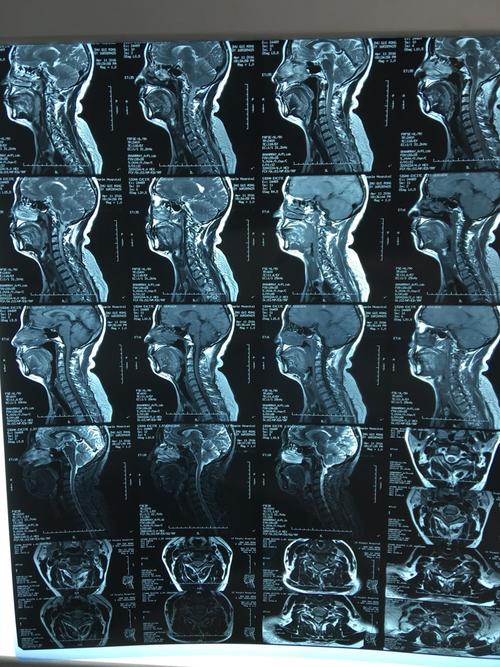

颈椎核磁图片,颈椎核磁共振图片

颈椎病专题(三):带你了解外伤后的颈脊髓损伤

颈椎核磁

颈椎3456向后轻微突出,前几天有呕吐,很严重吗?今天刚照的核磁.

眉县中医院骨二科成功完成-颈后路单开门减压内固定术治疗颈椎管狭窄

颈椎核磁片显示:颈4,5,6,7位颈椎间盘突出!

颈椎核磁共振图片

正常的颈椎核磁图片

正常颈椎核磁共振图

颈椎核磁共振图片图解

怎样看懂颈椎磁共振图

颈椎磁共振图片详解

颈椎核磁图片正常

颈椎核磁图片怎么看

颈椎核磁正常

颈椎核磁解剖

颈椎核磁图谱解析

颈椎的核磁共振的图解

颈椎核磁共振报告

磁共振颈椎神经压迫图